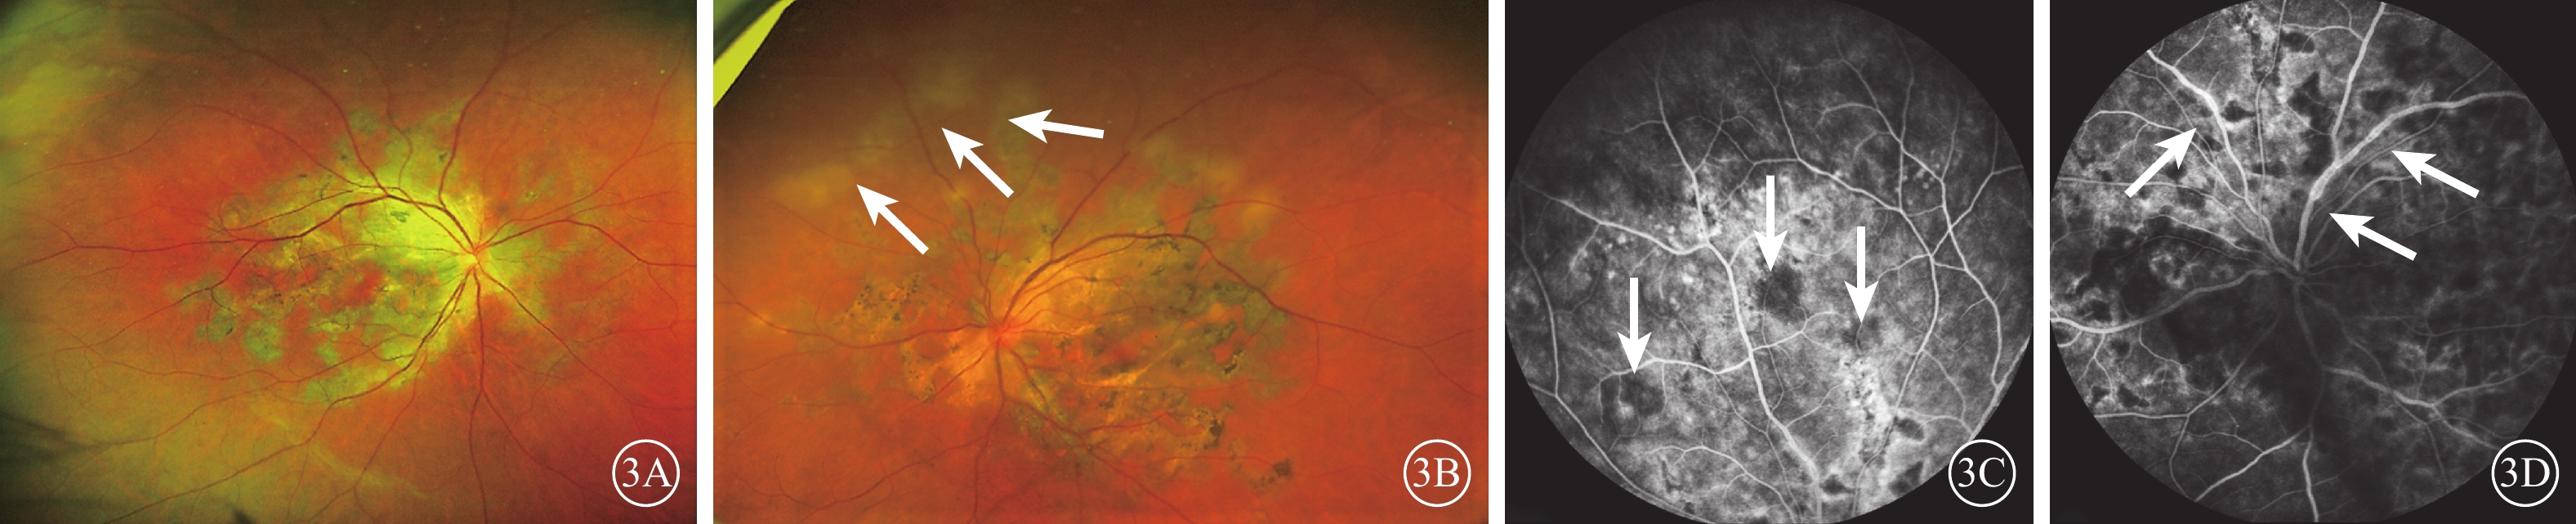

5例9只眼中,單眼1例1只眼,患者主述視力下降1個月余就診;雙眼4例8只眼,既往均診斷為雙眼急性后極部多灶性鱗狀色素上皮病變(APMPPE),其后6個月至2年因單眼視力下降再次就診時確診為急性多灶型SC。所有患眼均為后極部多發性大小不等、灰白色伴色素沉著、邊緣清晰的陳舊性RPE及脈絡膜毛細血管萎縮病灶(圖3A),其中陳舊性病灶附近出現多個新的活動性病灶4只眼(均為雙眼患者的其中1只眼),與陳舊性病灶相連或孤立存在,顏色灰白且邊界不清楚,扁平如“鱗狀”(圖3B)。眼底AF檢查,陳舊性病灶為弱AF;活動性病灶AF輕度增強。FFA檢查,陳舊性病灶呈邊界清晰的弱熒光斑,邊緣晚期熒光素著染形成強熒光環;活動性病灶呈邊緣模糊的弱熒光斑,晚期熒光略有增強(圖3C)。OCT檢查,活動性病灶患眼可見黃斑外層水腫,而后極部陳舊性病灶區光感受器層、RPE及脈絡膜萎縮,部分區域RPE增生。

輕度玻璃體炎5只眼,其中盤周型、黃斑型新發病灶各2只眼,急性多灶型復發病灶1只眼。炎癥表現為玻璃體浮游細胞4只眼,輕度絮狀混濁為1只眼(圖3D)。

視網膜血管炎3只眼。其中,黃斑型1只眼,可見視網膜血管白鞘及點狀出血;FFA檢查血管未見熒光素滲漏,提示為陳舊性病變;活動性急性多灶型、復發性盤周型各1只眼,表現為后極部視網膜靜脈管壁節段性輕度強熒光(圖3D)。